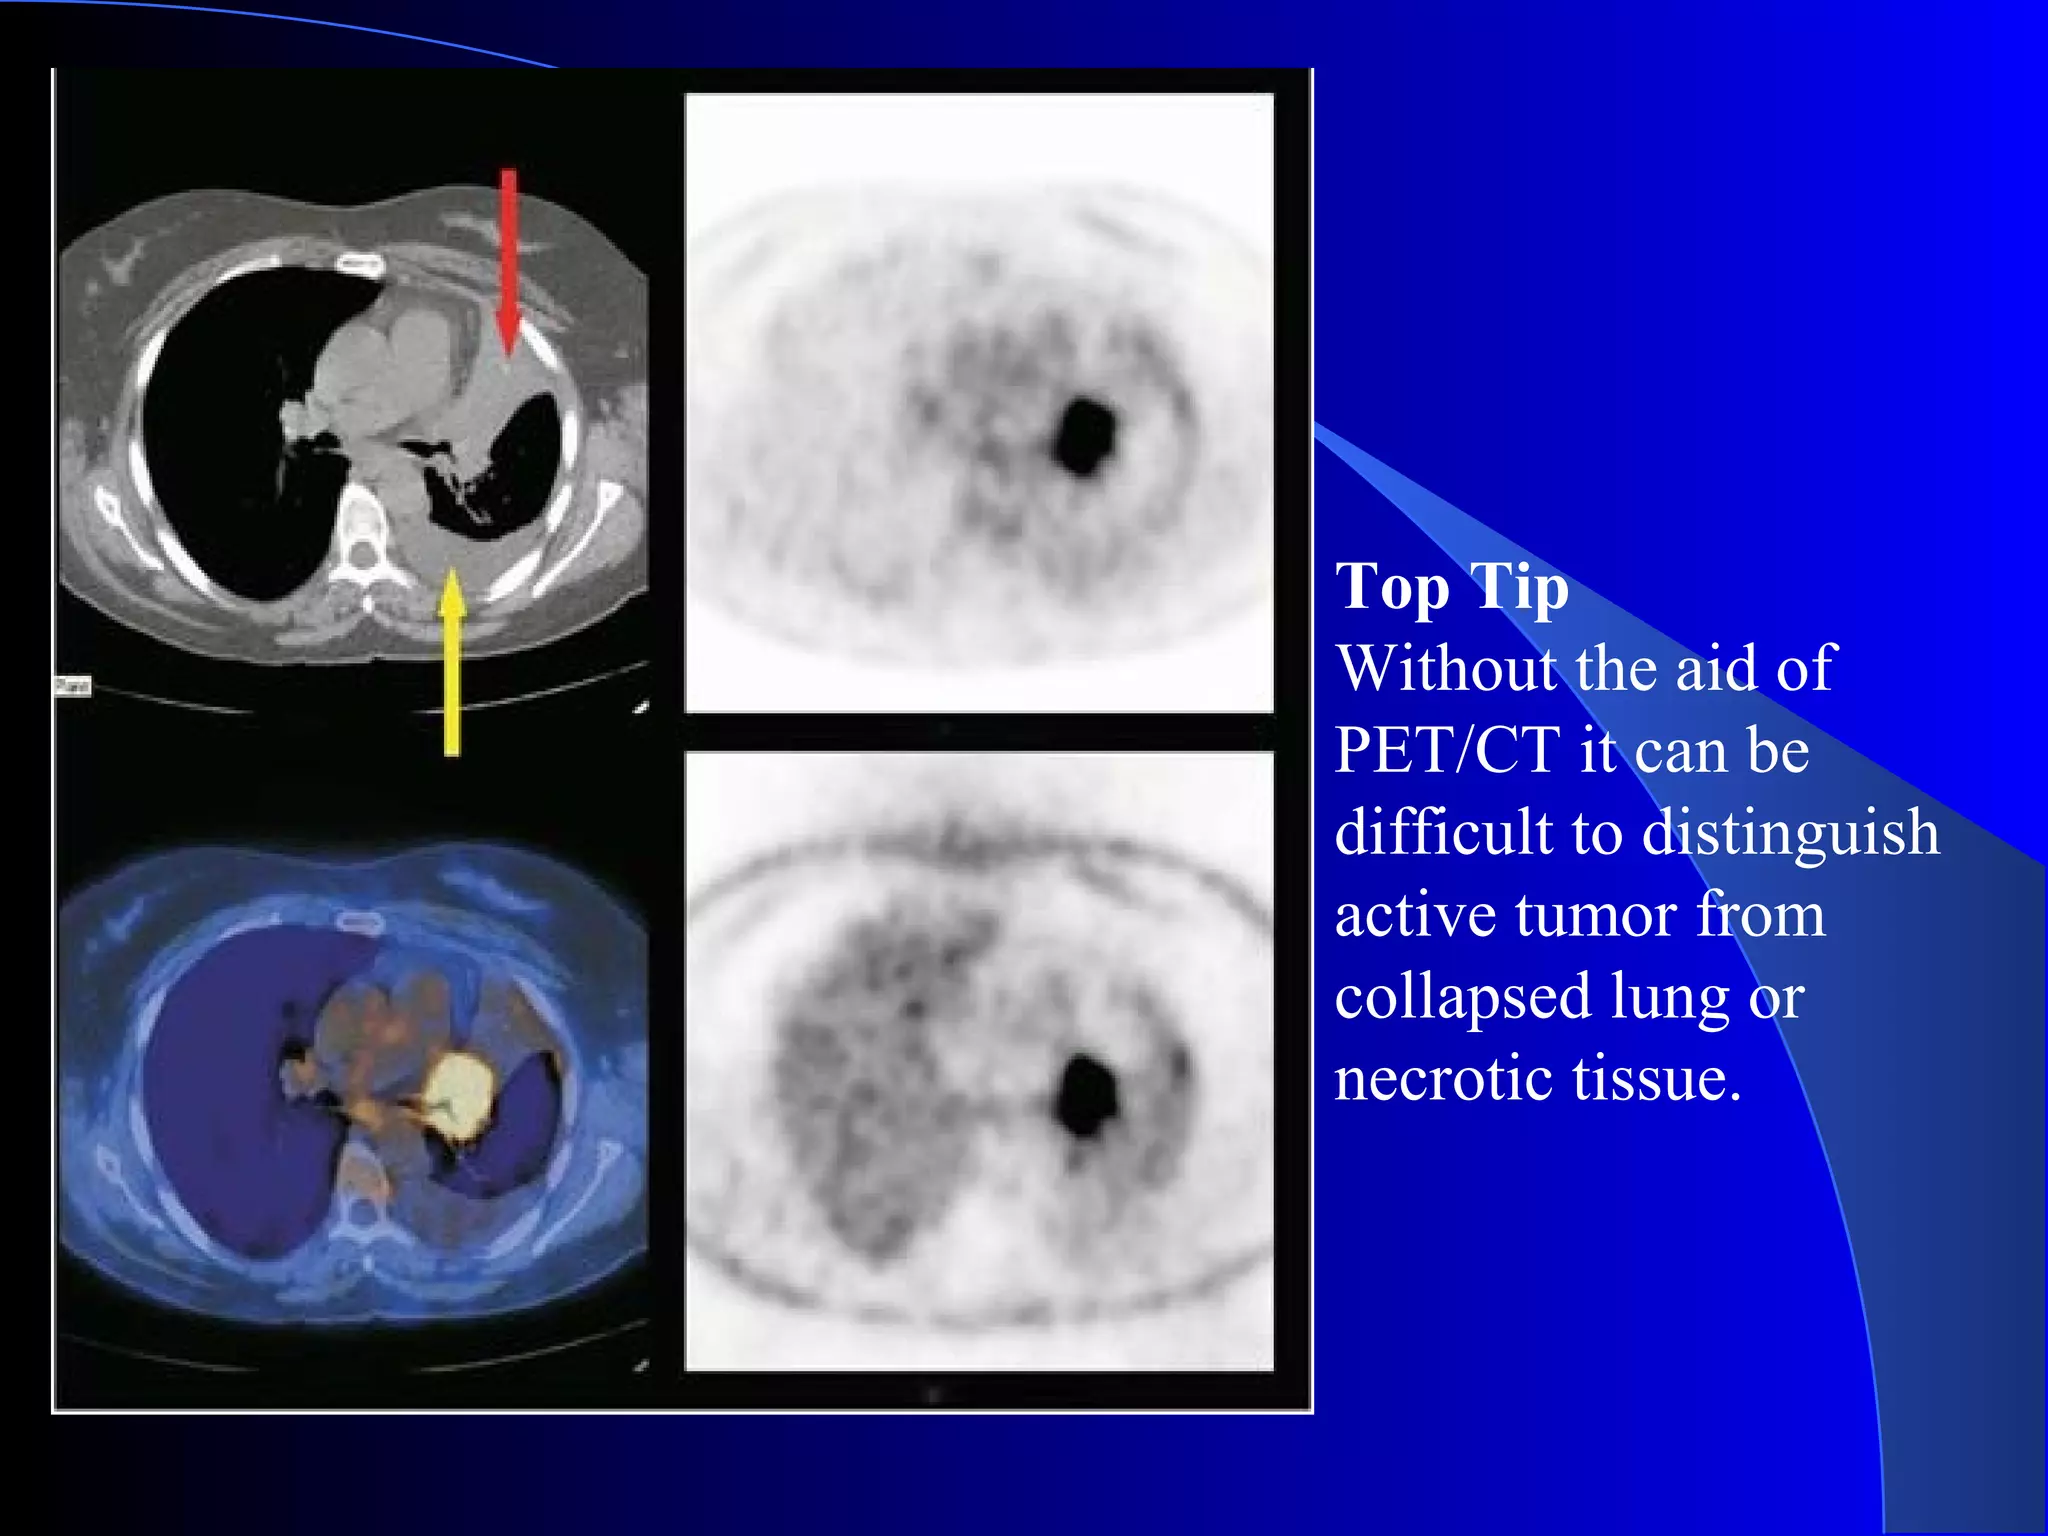

Top Tip

Without the aid of

PET/CT it can be

difficult to distinguish

active tumor from

collapsed lung or

necrotic tissue.

Patient for radiotherapy. Where does the tumor end and the

collapsed lung begin ?